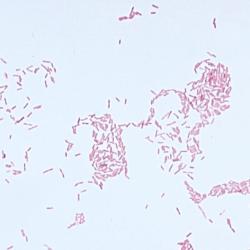

A Gram stain is used to determine if bacteria are present in an area of the body that is normally sterile, such as spinal fluid. A sample from the infected area is smeared on a glass slide and allowed to dry. A series of stains are applied and then the stained slide is examined under a microscope where bacteria appear either purple (gram positive) or pink (gram negative). The test is named after Dr. Christian Gram, who invented the process.

A Gram stain can predict the type of bacteria causing an infection, such as pneumococcal pneumonia or a staphylococcal abscess. Viruses cannot be seen with a Gram stain since they lack the cell wall, which takes up the stain.